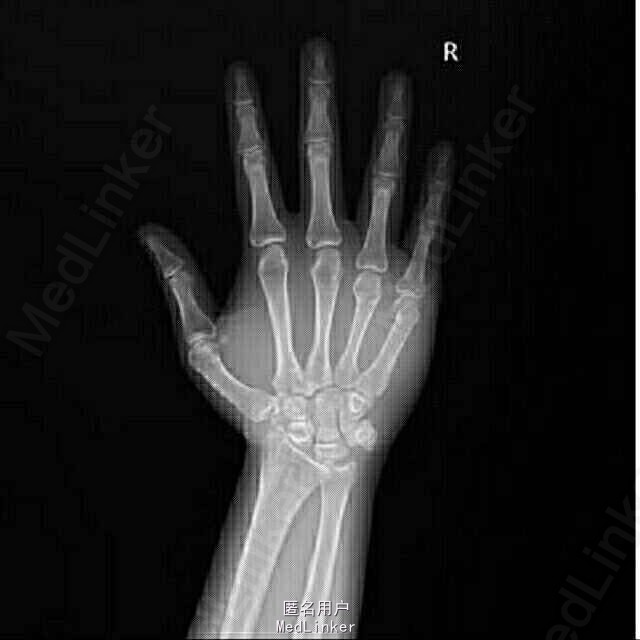

查体:第4、5掌指关节轻度肿胀,关节压痛(+),活动受限; 辅助检查:X线检查示:右手第4、5掌骨颈骨折,其中第5掌骨颈移位明显。

诊断:右第四、五掌骨颈骨折 行切开复位内固定术(LCP, Synthes, Titanium)